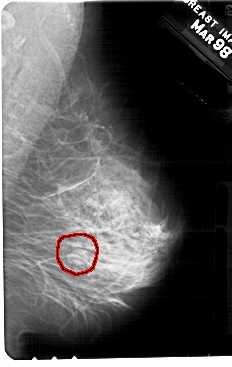

A_1363_1.RIGHT_MLO

RIGHT_MLO LINES 5491 PIXELS_PER_LINE 3466 BITS_PER_PIXEL 12 RESOLUTION 43.5 OVERLAY

FILE: A_1363_1.RIGHT_MLO.OVERLAY

TOTAL_ABNORMALITIES 1

ABNORMALITY 1

LESION_TYPE MASS SHAPE OVAL MARGINS CIRCUMSCRIBED-OBSCURED

ASSESSMENT 4

SUBTLETY 4

PATHOLOGY BENIGN

TOTAL_OUTLINES 1

BOUNDARY